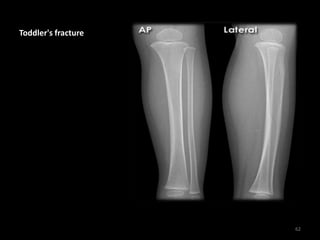

Toddler's fracture

60

• Fine spiral line through

the tibial shaft

• This toddler presented

with refusal to weight-

bear

61

62

63